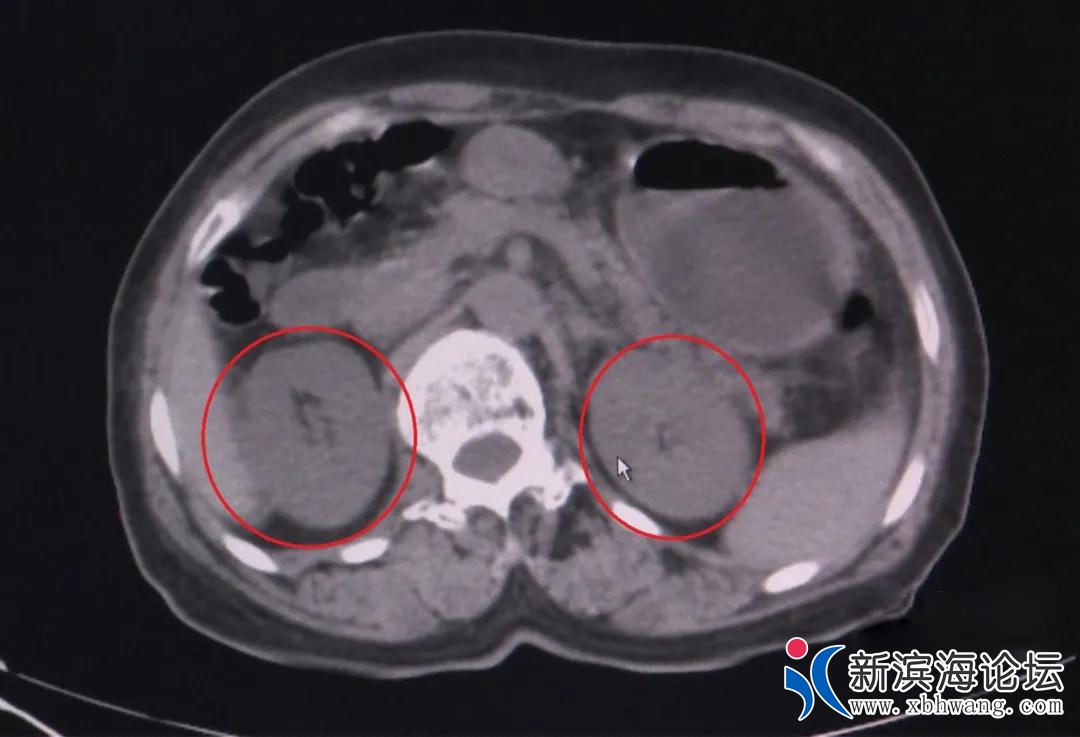

于是,李阿姨赶到了海宁市中医院(市肿瘤医院),接诊的海宁市中医院肾内科主任鄢胜刚检查后发现,李阿姨的肾功能指标已经达到了肾功能衰竭第五期,就是我们俗称的尿毒症期。

“这是典型的食物中毒!”鄢医生说,刀豆中含有生物碱,加热可分解。但李阿姨吃了整盘没烧熟的刀豆,毒素吸收导致急性肾功能衰竭,不能正常产生尿液,体内肌酐、尿素、氮尿酸等代谢废物无法排出。反映肾功能的肌酐指标一度飙升到600多,超出正常值上限的6倍。如不及时治疗,有突然心跳停止、血循环消失、休克的危险。住院后,李阿姨接受了血液透析治疗.